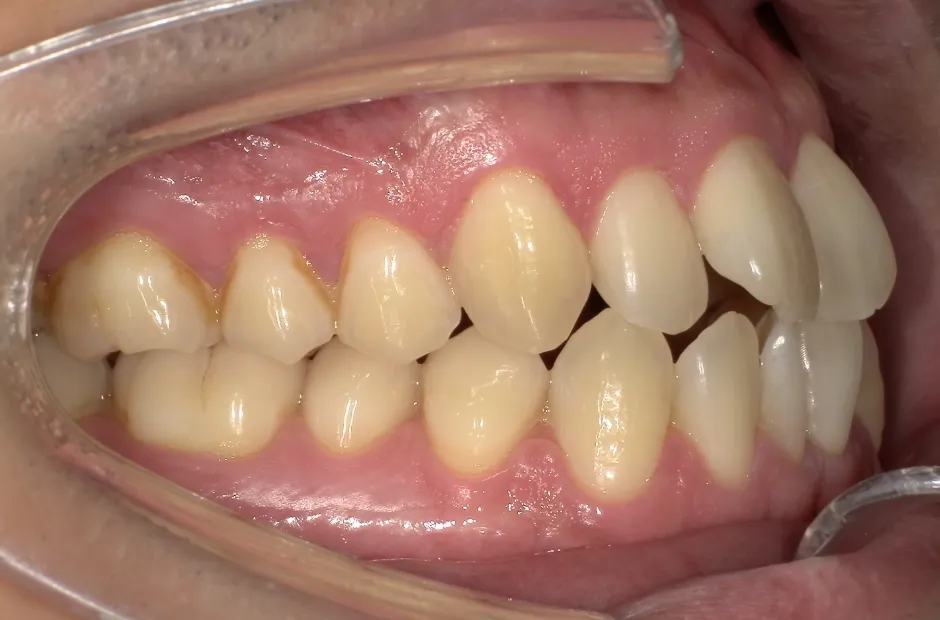

叢生

| 診断名・主訴 | 叢生 |

|---|---|

| 年齢・性別 | 43歳・女性 |

| 治療期間・回数 | 2年7か月 27回 |

| 治療に用いた主な装置 | 舌側矯正 |

| 抜歯部位 | 両顎4,4 |

| 治療費 | 100万円(税抜) |

| リスク・副作用 | 装置による違和感・疼痛・歯肉退縮・歯根吸収・虫歯のリスクなど |

治療前

治療後